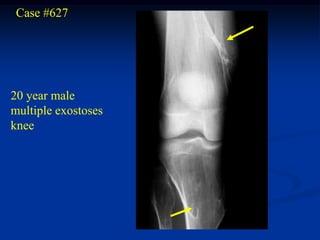

Case #627

20 year male

multiple exostoses

knee

Lateral view